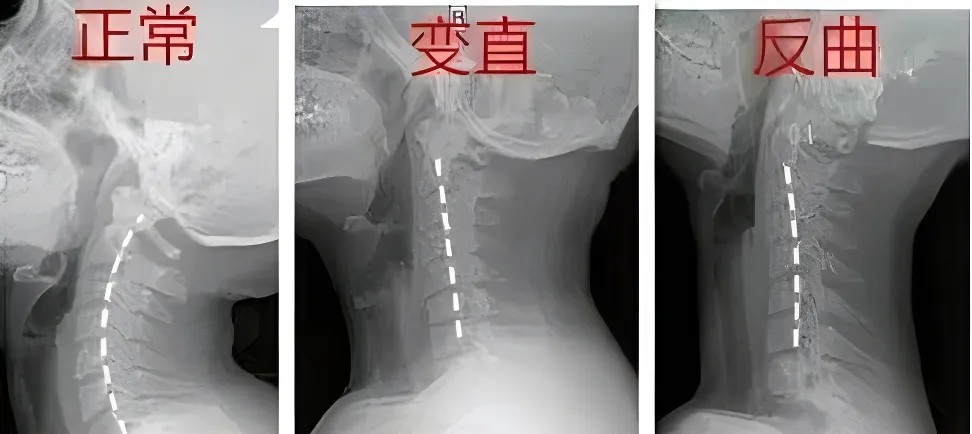

這些報(bào)告單上,常寫著“頸椎曲度(弧度)消失”、“頸椎變直”或者是“頸椎曲度反弓”,很多人看到后,一下子就慌了:這頸椎出問題可不是小事,曲度是什么呢?

嬰兒在學(xué)習(xí)爬行和抬頭的過程中,頸椎的生理曲度逐漸形成,在頸部呈現(xiàn)出一個(gè)開口向身體背側(cè)的“C”形;

脊柱的生理曲度就像彈簧一樣,它的存在能有效減輕外力的沖擊震蕩,保護(hù)脊髓和大腦,維持姿勢(shì)的穩(wěn)定。